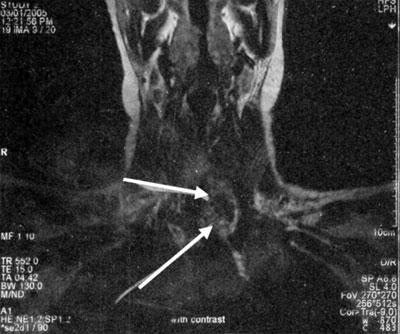

A 27-year old woman presented with a recent onset of a painless mass in the left side of her lower neck. The patient was asymptomatic and there was nothing significant in her past medical history except for iron deficiency anemia. On examination she was found to have an approximately 3 cm soft, mobile, non-tender mass in her lower neck. Thyroid function tests were normal; TSH was 1.0 mU/L (normal range 0.3-4.5), FT4 1.3 ng/dl (0.8-2), FT3 3.4 pg/ml (1.8-5). Thyroid hormones and TSH were measured by electrochemiluminescence immunoassay (ECLIA). Calcitonin, calcium, and PTH levels were normal. An ultrasound of her neck showed a multinodular goiter with 3 solid nodules on the left lobe of the thyroid, with a diameter of 1, 0.7, and 0.5 cm, respectively. A 3.4 cm solid mass of heterogeneous echotexture was identified in the left lower cervical area below the left lobe of the thyroid, separate from the thyroid, behind the sternoclidomastoid muscle with peripheral and internal flow signals. The patient refused a fine needle aspiration. An MRI scan of her neck showed a 2.5x2.2x3.5 cm well defined mass below the left lobe of the thyroid on the border between the cervix and the thorax, extending retrosternally (Figure 1, 2). The mass was suppressing the trachea but was not causing narrowing of the trachea. The mass appeared heterogeneous with hypervascularity. In the left lobe of the thyroid nodules 0.5-1 in diameter were also noted.

Figures 1 & 2. Transverse and coronal section of MRI scan of the neck showing a 2.5x2.2x3.5 cm heterogeneous mass below the left lobe of the thyroid on the border between the neck and the thorax, extending retrosternally.